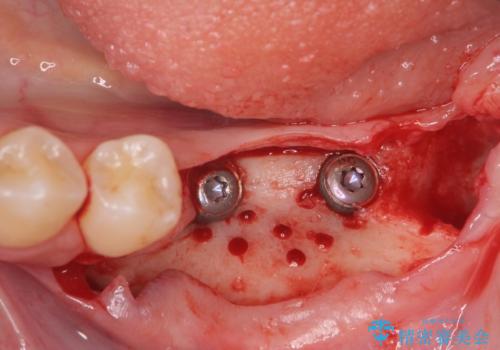

骨造成を行い安定したインプラントの環境を整える治療を計画します。

- 80万円(インプラント×2・骨造成・アバットメント×2)・ジルコニアクラウン×2)費用は治療当時の料金となります

インプラントの長期的な予後を見込むには、インプラント周囲の安定した十分な骨量や清掃性、角化歯肉の存在が重要です。